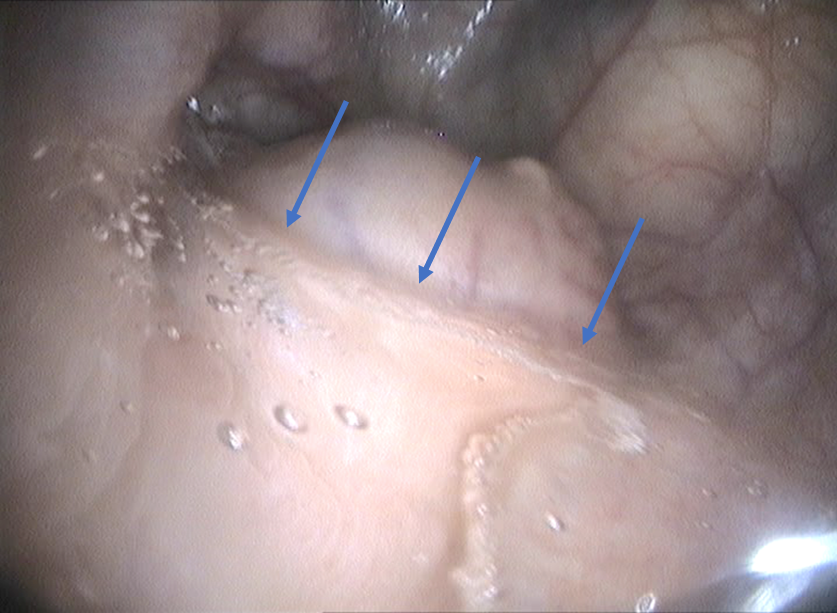

In this disease the thin lining of the guttural pouch becomes inflamed and the guttural pouch becomes filled with thick pus. These bacteria cause a large amount of mucus that contains white blood cells bacteria and necrotic. Strangles is tricky because about one in 10 otherwise fully recovered horses can become a carrier for the disease. The fungus has an affinity for growing on the surface of the guttural pouch overlying the nerves and arteries.

It has been shown that 10 percent of horses affected in a strangles outbreak can have a failure of guttural pouch drainage and therefore be at risk of carrier status newton et al 1998 to confirm clearance guttural pouch washes can be started three weeks after resolution of clinical signs and one lavage that is pcr negative confirms clearance of disease. After a positive or inconclusive grey area pre movement strangles blood test. The bacteria that causes strangles streptococcus equi is a major cause of infection in a horse s guttural pouch. If a horse s retropharyngeal lymph nodes drain backwards into the guttural pouches the pus can sit there and sometimes create hard lumps called chondroids.

This is caused by a bacterial infection usually secondary to strangles. Streptococcus equi is the most common organism involved and the infection may follow a case of strangles. When pus develops in the pouches the condition is known as guttural pouch empyema and often occurs following an infection of the pharynx. This leads to a horse becoming known as a carrier of strangles.